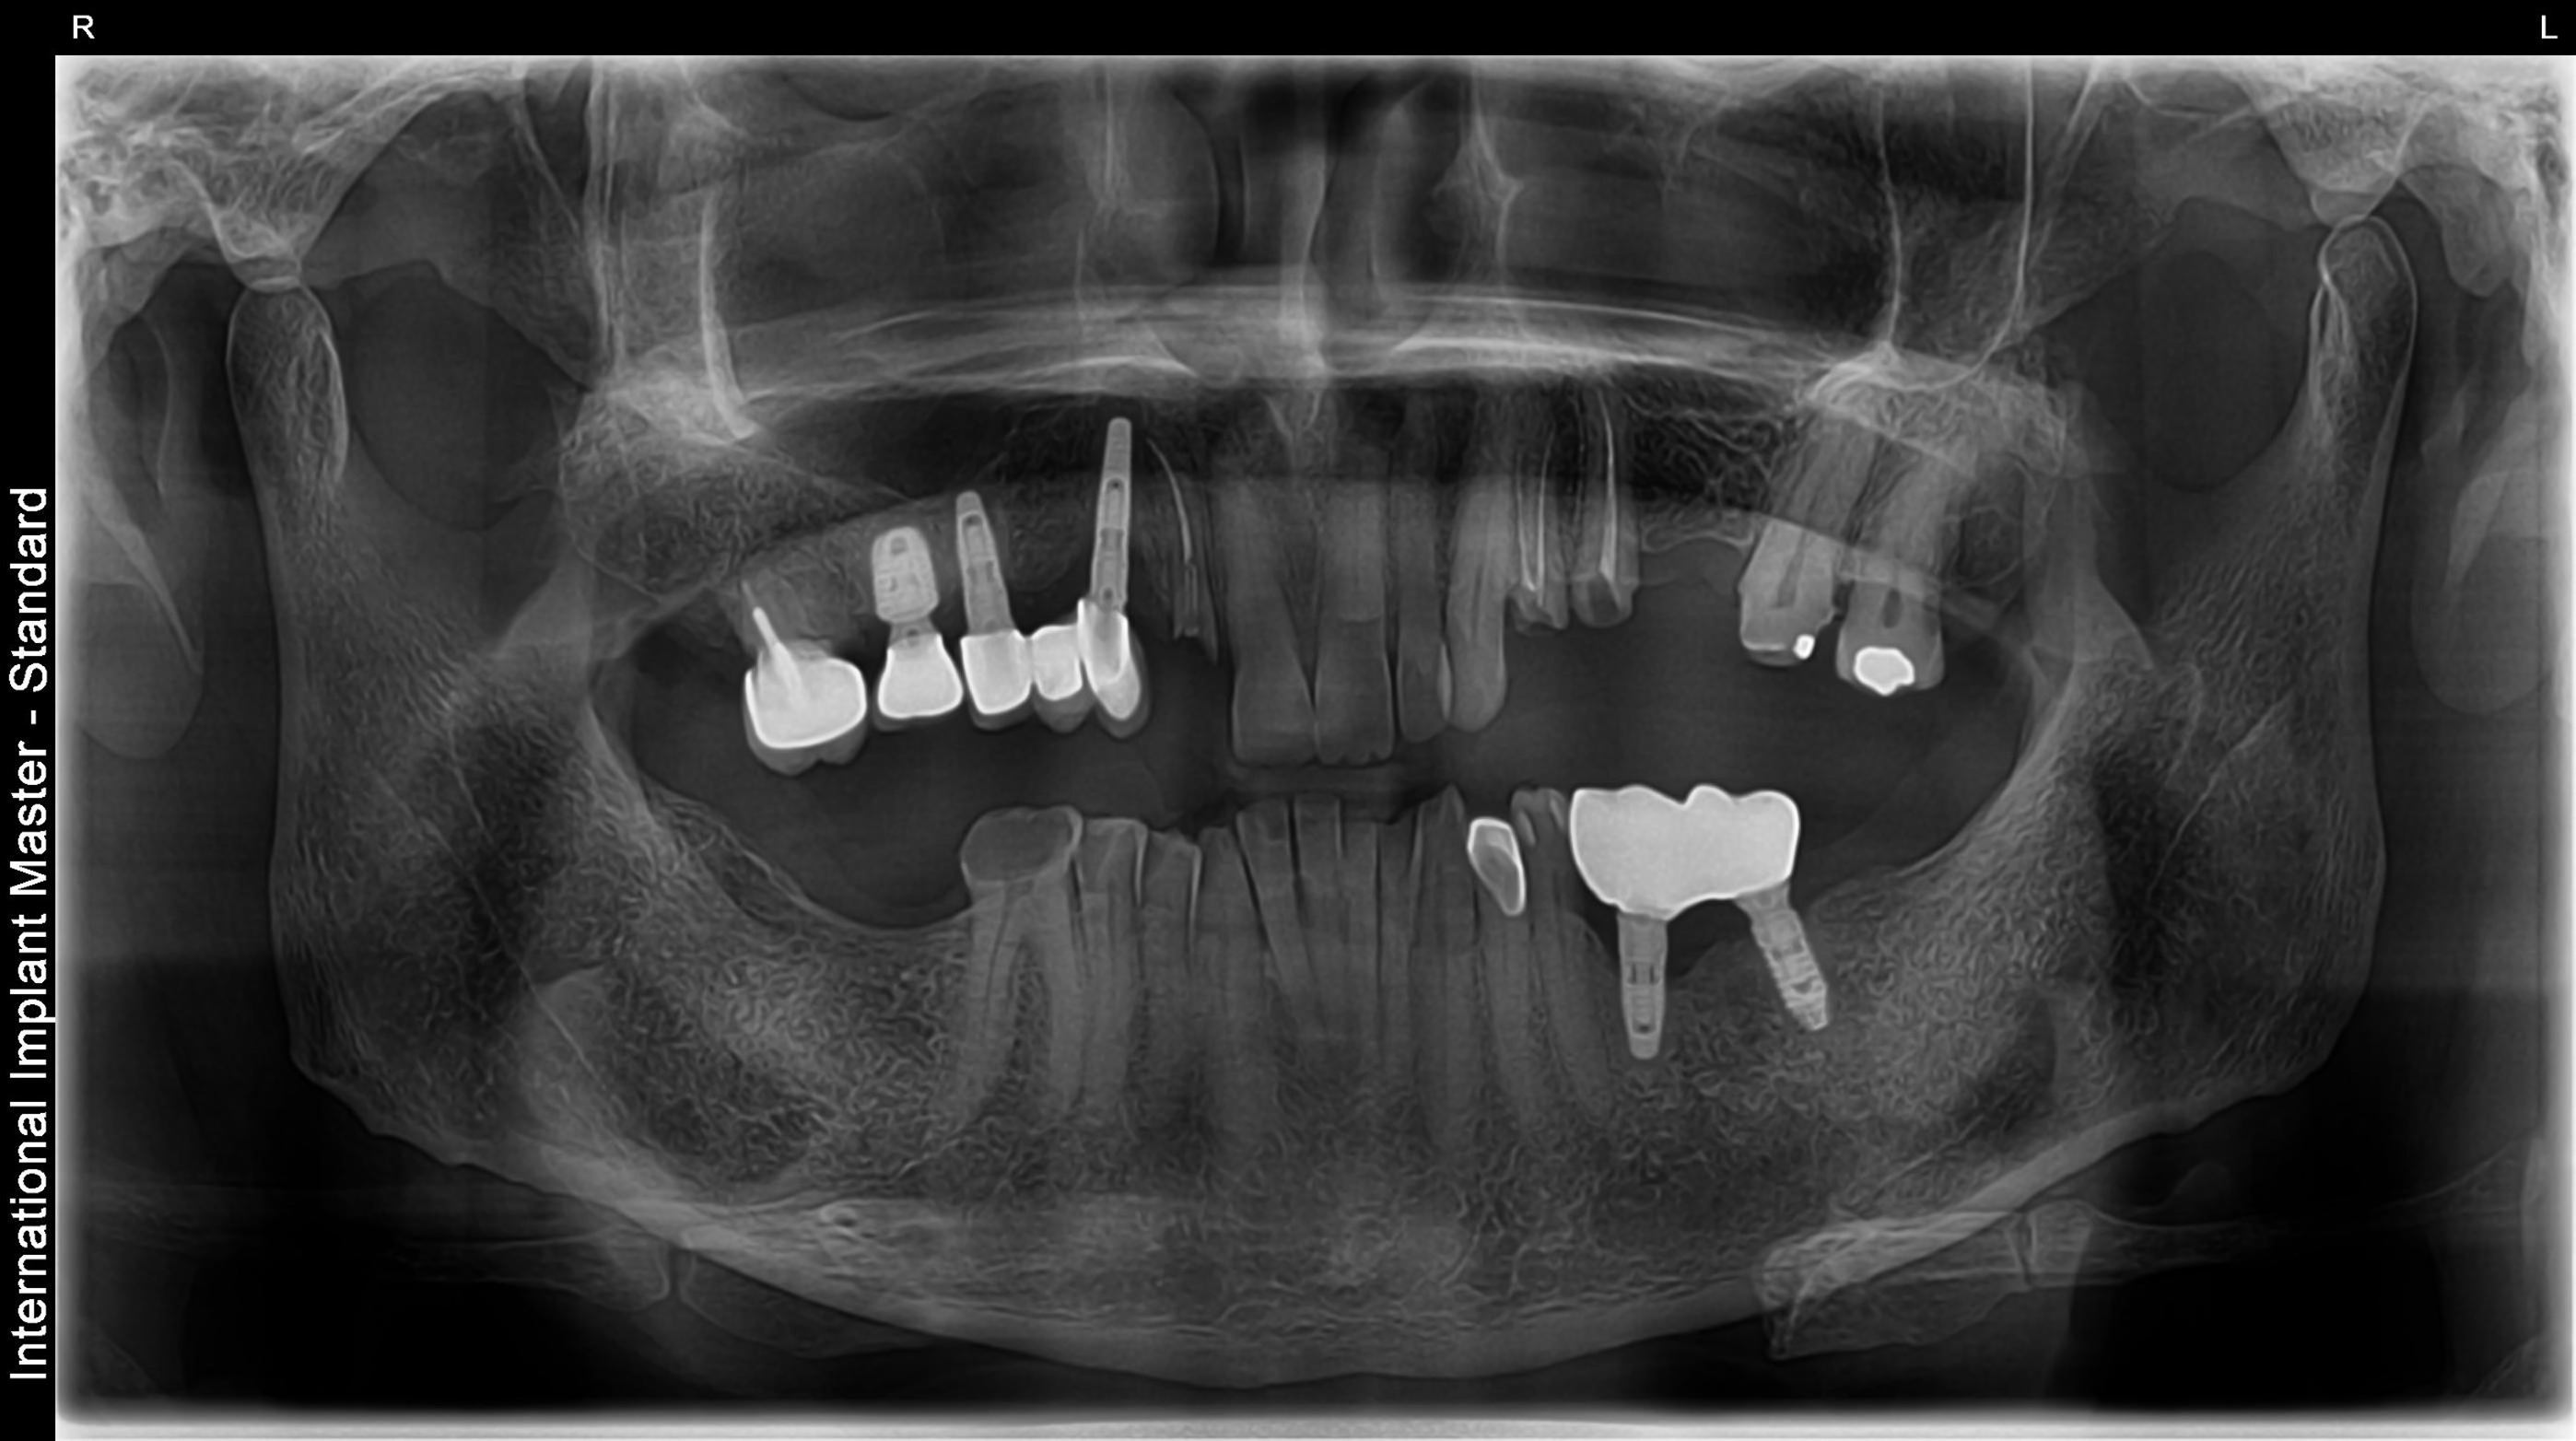

Full Mouth Rehabilitation

This includes comprehensive dental work such as implants, crowns, root canals, and other restorations to fully restore dental health and aesthetics.

Before vs After Xrays